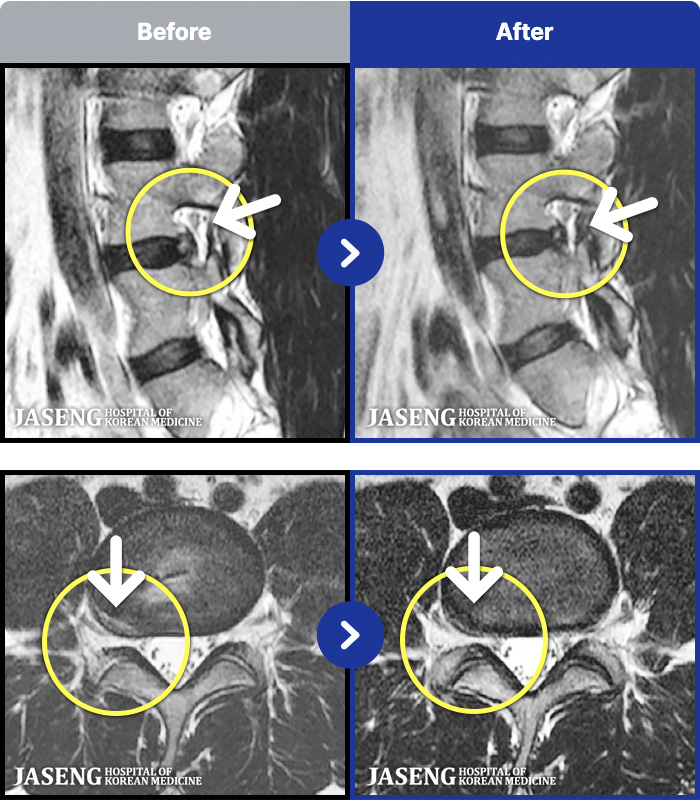

1,237 MRI ũ ʸ Ȯϼ.

1,237